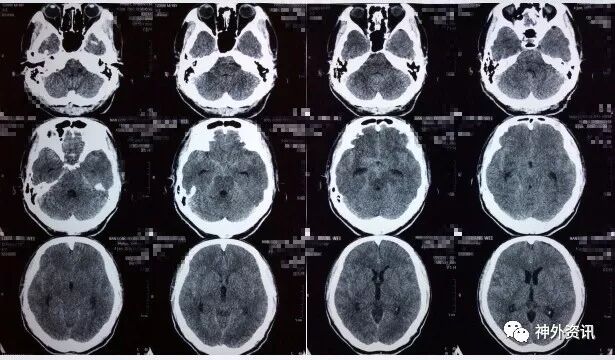

患者缘于10天前无明显诱因突发头痛伴呕吐,于当地医院就诊查头部CT提示:SAH;遂于当地医院予以保守治疗,其后症状逐渐好转;于发病9天后突然出现右眼眼睑下垂及右眼视物不清,遂到河北医科大学第二医院东院区就诊。头部CT提示未见明显出血;头部CTA提示:右侧后交通动脉动脉瘤及左侧脉络膜前动脉动脉瘤。

发病当天CT

发病后9天CT